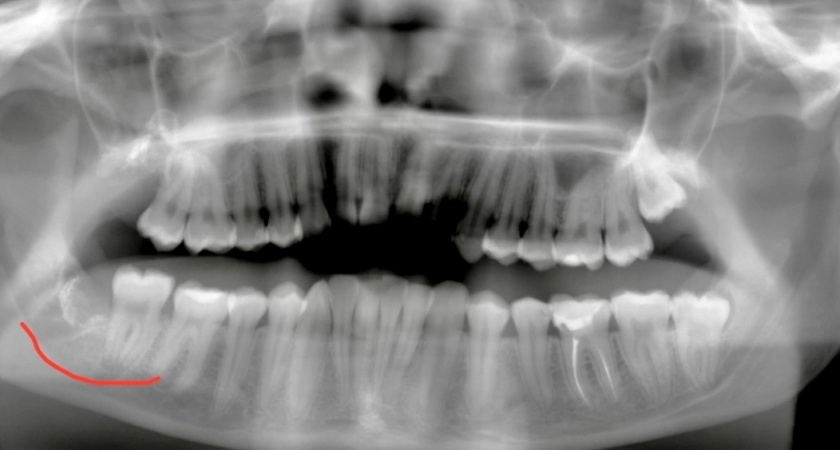

В Нижнем Новгороде хирурги Областной стоматологической поликлиники на Покровке успешно провели операцию по пересадке собственного зуба пациенту. Этот метод называется аутотрансплантацией и представляет собой альтернативу традиционной имплантации. Об этом сообщает Алексей Никонов .

Не всегда необходимо ставить имплант, иногда на место удаленного разрушенного зуба можно пересадить наш же зуб мудрости. Так произошло и с пациентом Областной стоматологической поликлиники на Покровке. Ему вместо удаленного разрушенного зуба хирурги пересадили его же зуб мудрости.

Такой альтернативный метод имплантации называется аутотрансплантацией - когда человеку пересаживают его же ткани, в данном случае зуб.